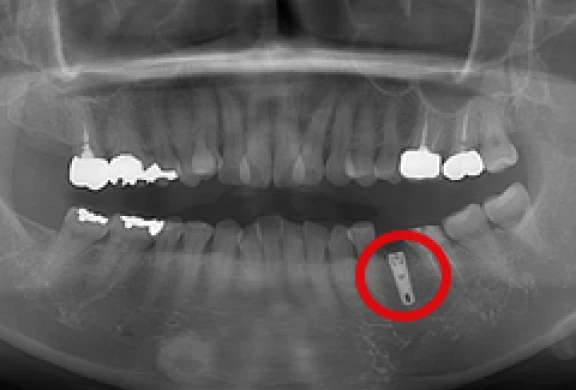

インプラントの埋め込み

-

上部構造の装着

パノラマ

歯間部のインプラント

(上部構造の装着)